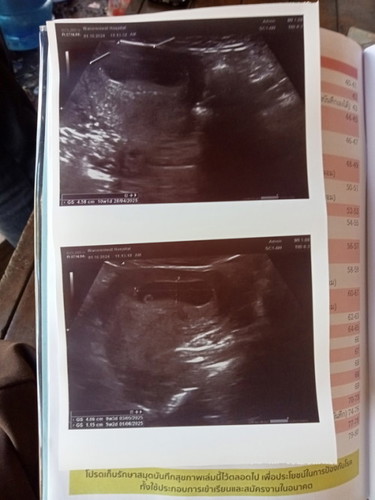

แม่ๆคนไหนเคยเจอแบบนี้ไหมค่ะเจอถุงตั้งครรภ์และถุงไข่แต่ยังไม่เจอตัวน้องหมอบอกอาจจะท้องลมได้แต่นัดอีก

นัดอีก2 อาทิตย์อาจจะเป็นท้องลมได้ไหมค่ะ ซาวรอบแรก7สัปดา5วันค่ะแต่หมอบอกยังไม่แน่ชัด